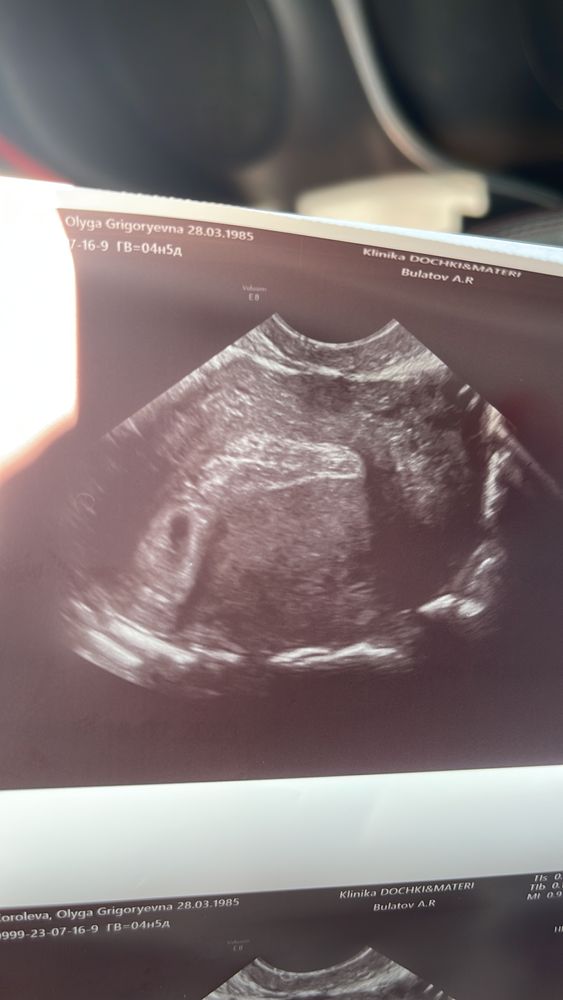

17 дпп Узи💕💕💕

Это отличные новости даже эмбриончика увидели 🥰🙏👼🏼первое фото малышки 🌺🌺🌺

16.07.2023

Наиля , сама честно не ожидала но ждала🙏🙏🙏Дай бог и дальше все будет хорошо🙏🙏🙏❤️